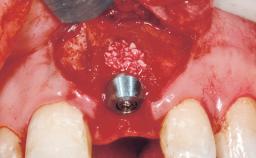

A 42-year-old female patient was referred to our clinic at the School of Dentistry of the University of São Paulo in November 2004, presenting a deficient restoration in the upper left central incisor. The clinical examination revealed no gingival retraction or any signs of gingival inflammation and, therefore, previous periodontal treatment was not considered. The patient presented a high lip line at full smile and a thin tissue biotype. This combination characterized a high-risk situation from an anatomic point of view, which required careful preoperative planning and cautious surgical execution.

Placement Protocol Immediate implant placement

Socket Integrity Sufficient, with intact bone walls

Bone Volume Sufficient, with intact walls

Loading Protocol Immediate